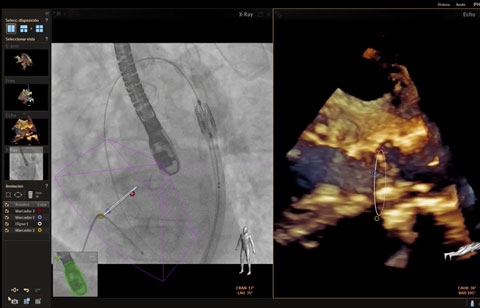

تساعدك القياسات الدقيقة للقوس الأورطي باستخدام البيانات ثلاثية الأبعاد في اختيار حجم الجهاز المناسب.

متابعة إجراءات التدخل وتقييمها من خلال الاتصالات الموسّعة بين أعضاء فرق طب القلب.

استخدام Live xPlane لتقييم النتائج. ما يتم عرضه هنا: عدم وجود تسريب في المنطقة المجاورة للصمام.